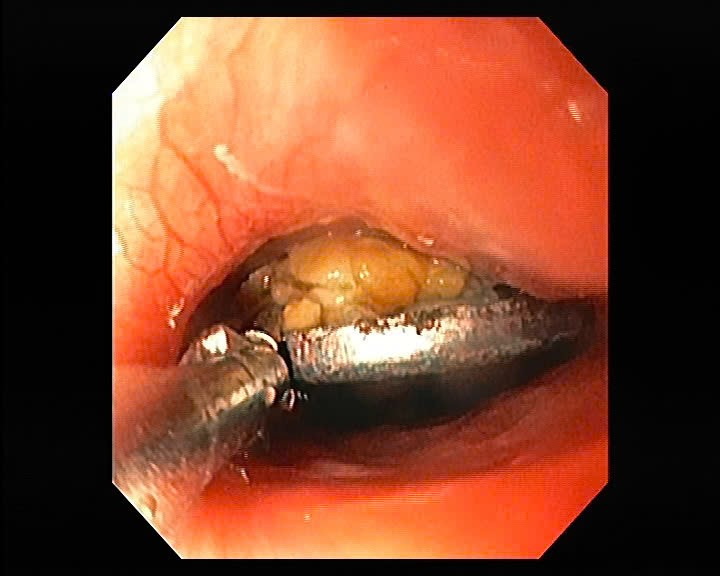

- Sau khi hội chẩn kỹ lưỡng, ekip nội soi tiêu hóa kết hợp cùng ekip gây mê hồi sức để tiến hành can thiệp gắp dị vật. Bác sĩ nội soi phát hiện tại thực quản, ngay dưới cơ thắt có 01 dị vật kim loại, gắp ra là 01 long đen kim loại hình tròn, có dấu hiệu han rỉ, đường kính 2,1cm. Niêm mạc thực quản chỗ dị vật mắc lại có 02 ổ loét sâu, kích thước ~ 2cm, có giả mạc trắng bám.